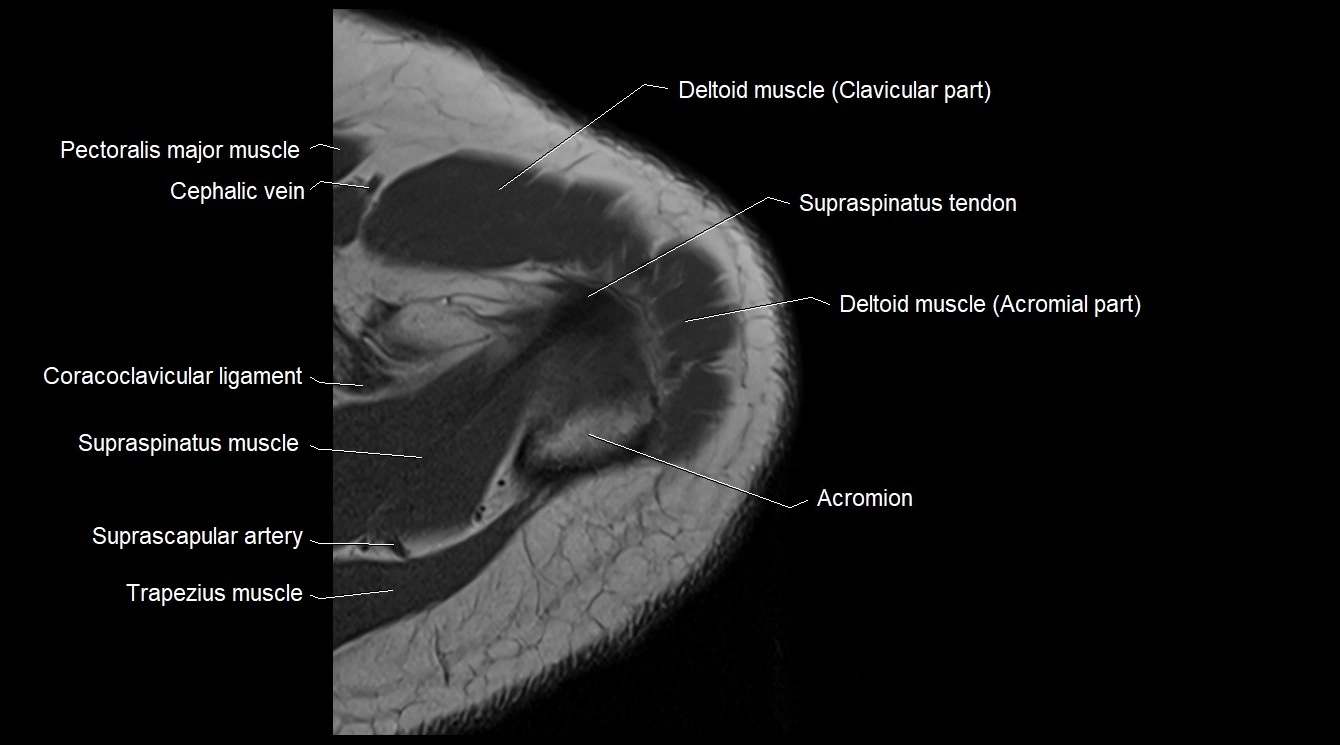

MRI image